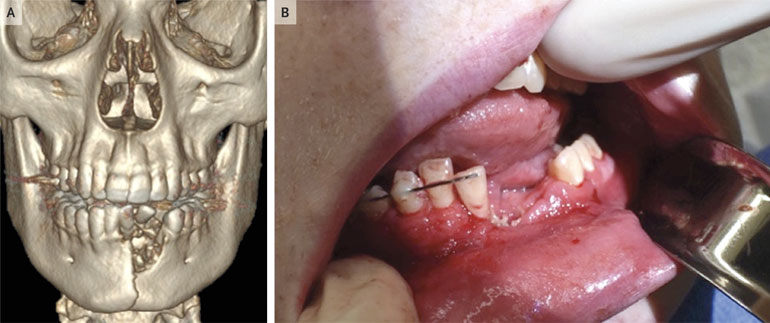

Un adolescent a eu la mâchoire explosée après l’explosion d’une cigarette électronique. Des cas de plus en plus fréquents. Kailani Burton qui vit a Salt Lake City aux États-Unis a acheté un kit de vaping pour son fils âgé de 17 ans dans l’espoir de le voir arrêter de fumer. Alors que les parents étaient assis dans le salon, ils ont entendu un gros bruit et ont vu surgir Austin, leur enfant avec la mâchoire ensanglantée. La cigarette électronique lui avait explosé dans la bouche. Cigarette electronique explosion Il manquait un bout de mâchoire ! "Il saignait beaucoup", raconte Kailani Burton dans une interview. "On aurait dit qu’il avait un trou dans le menton ». La famille se précipite à l'hôpital d'Ely, dans le Nevada, mais va au dégâts est orienté rapidement vers le centre de traumatologie de Salt Lake City. Cigarette electronique explosion Blessé et en sang, il raconte aux médecins avoir vu un gros éclair, puis ressenti une violente douleur dans la mâchoire inférieure, suite à quoi il a retiré l'appareil de sa bouche. Bilan : fracture majeure de la mâchoire inférieure et plusieurs dents de cassées. Aujourd’hui, il a besoin d'une plaque plaqué sous ses gencives pour stabiliser sa mâchoire et il lui a fallu 6 semaines avant qu’il puisse refermer sa bouche normalement. Cigarette electronique explosion La cigarette électronique est un produit de chez VGOD, qui vent tout une gamme d'appareils de vaping : Mango Bomb, Berry Bomb et Apple Bomb. Après expertise et enquête de la police, l’accident est du à la surchauffe du dispositif qui a fait exploser la batterie. Aux Etats-Unis, 2 035 cas d'explosion de cigarette électronique et de brûlures liées au vapotage ont été recensés en 2017. "Je ne savais pas que ces appareils pouvaient exploser et causer de graves blessures", explique le Dr Russell, directeur du centre de traumatologie du Primary Children's Hospital (Salt Lake Cit), qui a soigné Austin. "Mais le fait est qu'ils peuvent brûler. Ils peuvent exploser dans votre poche. Ils peuvent vous exploser à la figure. Je pense qu'il y a là un problème de santé publique".